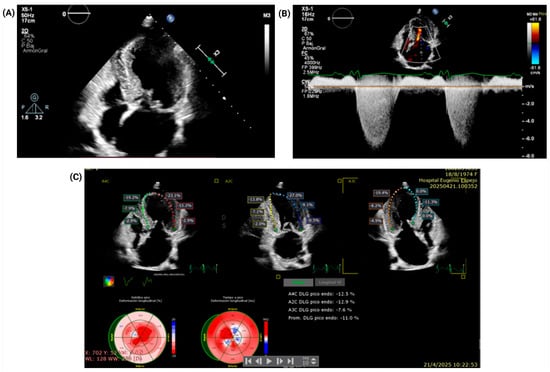

Combined Fixed and Dynamic Left Ventricular Outflow Tract Obstruction in Hypertrophic Cardiomyopathy Due to a Coexisting Subaortic Membrane: A Case Report

Introduction: Hypertrophic cardiomyopathy (HCM) is a common myocardial disease worldwide and is associated with heart failure symptoms and sudden cardiac death. In a subset of patients, it may produce dynamic left ventricular outflow tract obstruction (LVOTO) and systolic anterior motion (SAM)-related mitral valve dysfunction through drag forces and altered mitral–septal geometry. In contrast, subaortic stenosis caused by a subaortic membrane is an uncommon congenital lesion that may lead to fixed subvalvular LVOTO in adulthood. The coexistence of these entities is rare and can substantially complicate diagnosis and management. Case presentation: A 51-year-old woman with HCM, paroxysmal atrial fibrillation, and heart failure presented with acute decompensation and cardiogenic shock. After initial hemodynamic stabilization and cardioversion for atrial fibrillation with rapid ventricular response, multimodality imaging with transthoracic and transesophageal echocardiography, coronary computed tomography angiography, and cardiac magnetic resonance demonstrated dual LVOTO, with a dynamic component related to HCM/SAM physiology and a fixed component caused by an elongated subaortic membrane, accompanied by severe SAM-related mitral regurgitation. Echocardiography showed a resting peak LVOT gradient of 49 mmHg, increasing to 85 mmHg with the Valsalva maneuver. After exclusion of obstructive coronary artery disease and evaluation for selected phenocopies, the patient underwent septal myectomy, subaortic membrane resection, and adjunctive mitral valve plication. Early postoperative echocardiography showed reduction in the maximum provoked LVOT gradient to 38 mmHg and improvement of mitral regurgitation from severe to mild. At 3-month follow-up, she remained in sinus rhythm, improved to New York Heart Association functional class II, and had no documented readmissions for heart failure. Conclusions: Combined fixed and dynamic LVOTO due to concomitant subaortic membrane and HCM is exceedingly rare. Accurate diagnosis requires a high index of suspicion and a multimodality imaging strategy to define the obstructive mechanisms and support mechanism-based surgical management and avoid incomplete treatment when a coexisting fixed lesion is present. Full article

Figure 1